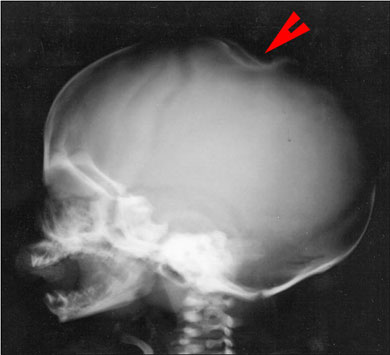

Le indagini laboratoristiche non presentano alterazioni significative, TAC, ecografia addominale ed ecocardiogramma risultano nella norma. L'esame radiologico dello scheletro evidenzia invece a livello della teca cranica una spiccata deformazione in corrispondenza della voluminosa lesione nodulare cutanea (Fig.3). ![]() |

Il caso presentato, che può essere certamente ascritto alla miofibromatosi congenita ad elementi multipli con esclusivo interessamento cutaneo, si caratterizza per la natura secondaria della lesione ossea radiologicamente documentata a carico della teca cranica (Fig.3). Come spesso accade il progressivo accrescimento di una lesione cutanea in forma nodulare e di consistenza dura o teso-elastica (sia essa un miofibroma o una lesione proliferativa di altra natura, una cisti dermoide malformativa o una semplice cisti sebacea) determina facilmente, in età pre e neonatale, una depressione corrispondente delle strutture ossee sottostanti, specie a livello del distretto cefalico.